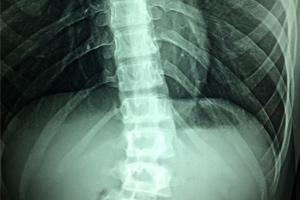

Mejora en pacientes parapléjicos crónicos

Mediante interfaces cerebro-máquina, retroalimentación visual-táctil y locomoción asistida